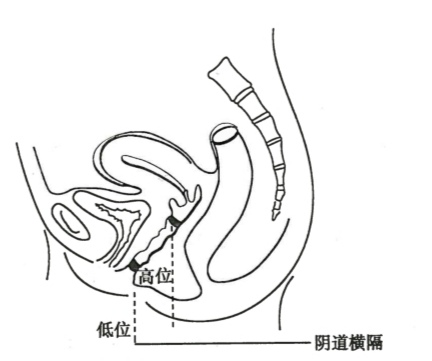

为泌尿生殖窦未参与形成阴道下段所致。根据阴道闭锁的解剖学特点可将其分为:①阴道下段闭锁,也称为阴道1型阴道闭锁,阴道上段及宫颈、子宫体均正常;②阴道完全闭锁,也称为阴道Ⅱ型阴道闭锁,多合并宫颈发育不良,子宫体发育不良或子宫畸形。

图22-3 阴道闭锁模式图

阴道下段闭锁因子宫内膜功能多为正常,因此症状出现较早,主要表现为阴道上段扩张,严重时可以合并宫颈、宫腔积血,妇科检查发现包块位置较低,位于直肠前方,无阴道开口,闭锁处黏膜表面色泽正常,亦不向外隆起,肛诊可扪及凸向直肠包块,位置较处女膜闭锁高。较少由于盆腔经血逆流引发子宫内膜异位症。阴道完全闭锁多合并宫颈发育不良,子宫体发育不良或子宫畸形子宫内膜功能不正常,经血容易逆流至盆腔,常常发生子宫内膜异位症。磁共振显像和超声检查可帮助诊断。